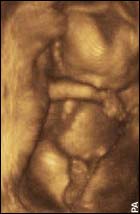

Six-week-old unborn baby

Surgical abortions seldom take place before the sixth to seventh week of pregnancy. At this time, the developing embryo already has a heartbeat and brain waves. The majority of abortions take place in the eighth to tenth week. At this stage, the unborn baby is called a fetus. At this time, the unborn baby already has fingers and toes, a face, and all of her organs. The organs may be primitive – but they are all there. The fetus, at this stage, is obviously human – you can tell by looking at it that it is not a dog fetus or a cat fetus, but a human fetus. It is a human unborn baby in an early stage of development.